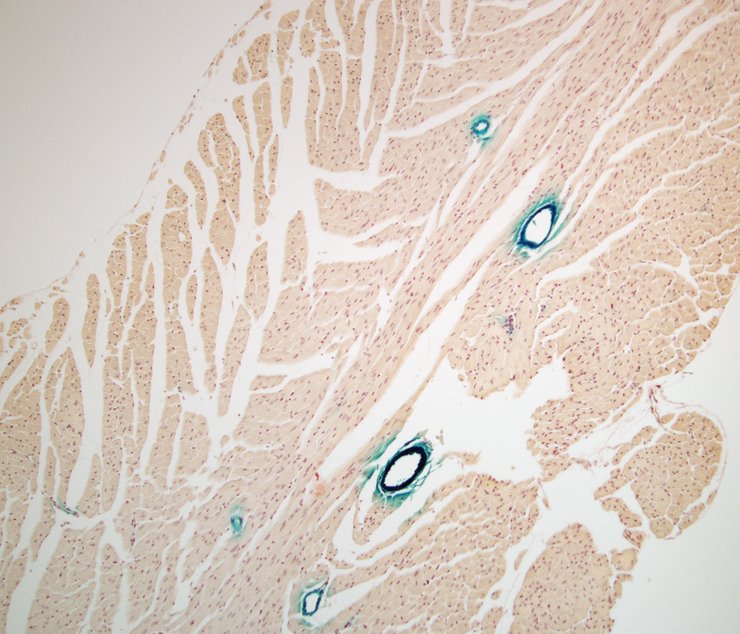

Assay type: In situ reporter (knock in)

Gene symbol: Tgfb3

Gene name: transforming growth factor, beta 3

Reporter: lacZ

TS28: vascular system Present TCP_2460741

TS28: vascular system Present TCP_2460736